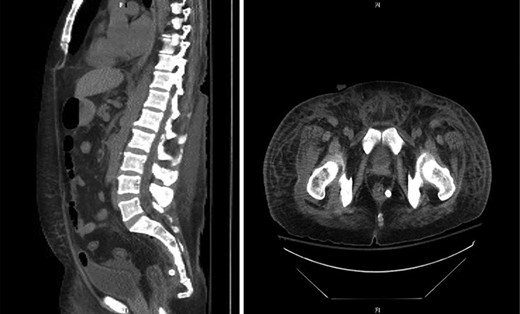

Marked improvement was seen on CT post-operative day 5 (Fig. 3). MRI of the pelvis showed marrow edema in the sacrum and coccyx, which was consistent with osteomyelitis and complex fluid collections of the right pelvis and right upper thigh, which was likely tracking from the presacral process. A CT guided drain placement was done for the right thigh abscess. Repeat MRI on day 14 showed resolution of the pelvic abscess, sacral osteomyelitis and myositis of the left gluteal and iliacus muscles. The patient was taken back to the OR to remove the rectal drain and replace it with a transperineal drain. This was carried out to allow the rectal perforation to heal and to provide continued drainage given the persistent myositis and osteomyelitis. The patient was started on steroids for his Crohn’s disease with plans to switch to biologic therapy. The transperineal drain was removed on post-operative day 25, and he was discharged home on biologic therapy with tapering of his steroid regimen.

Computed tomography (sagittal and axial views) showing post-operative resolution of the presacral abscess (post-operative day 5).